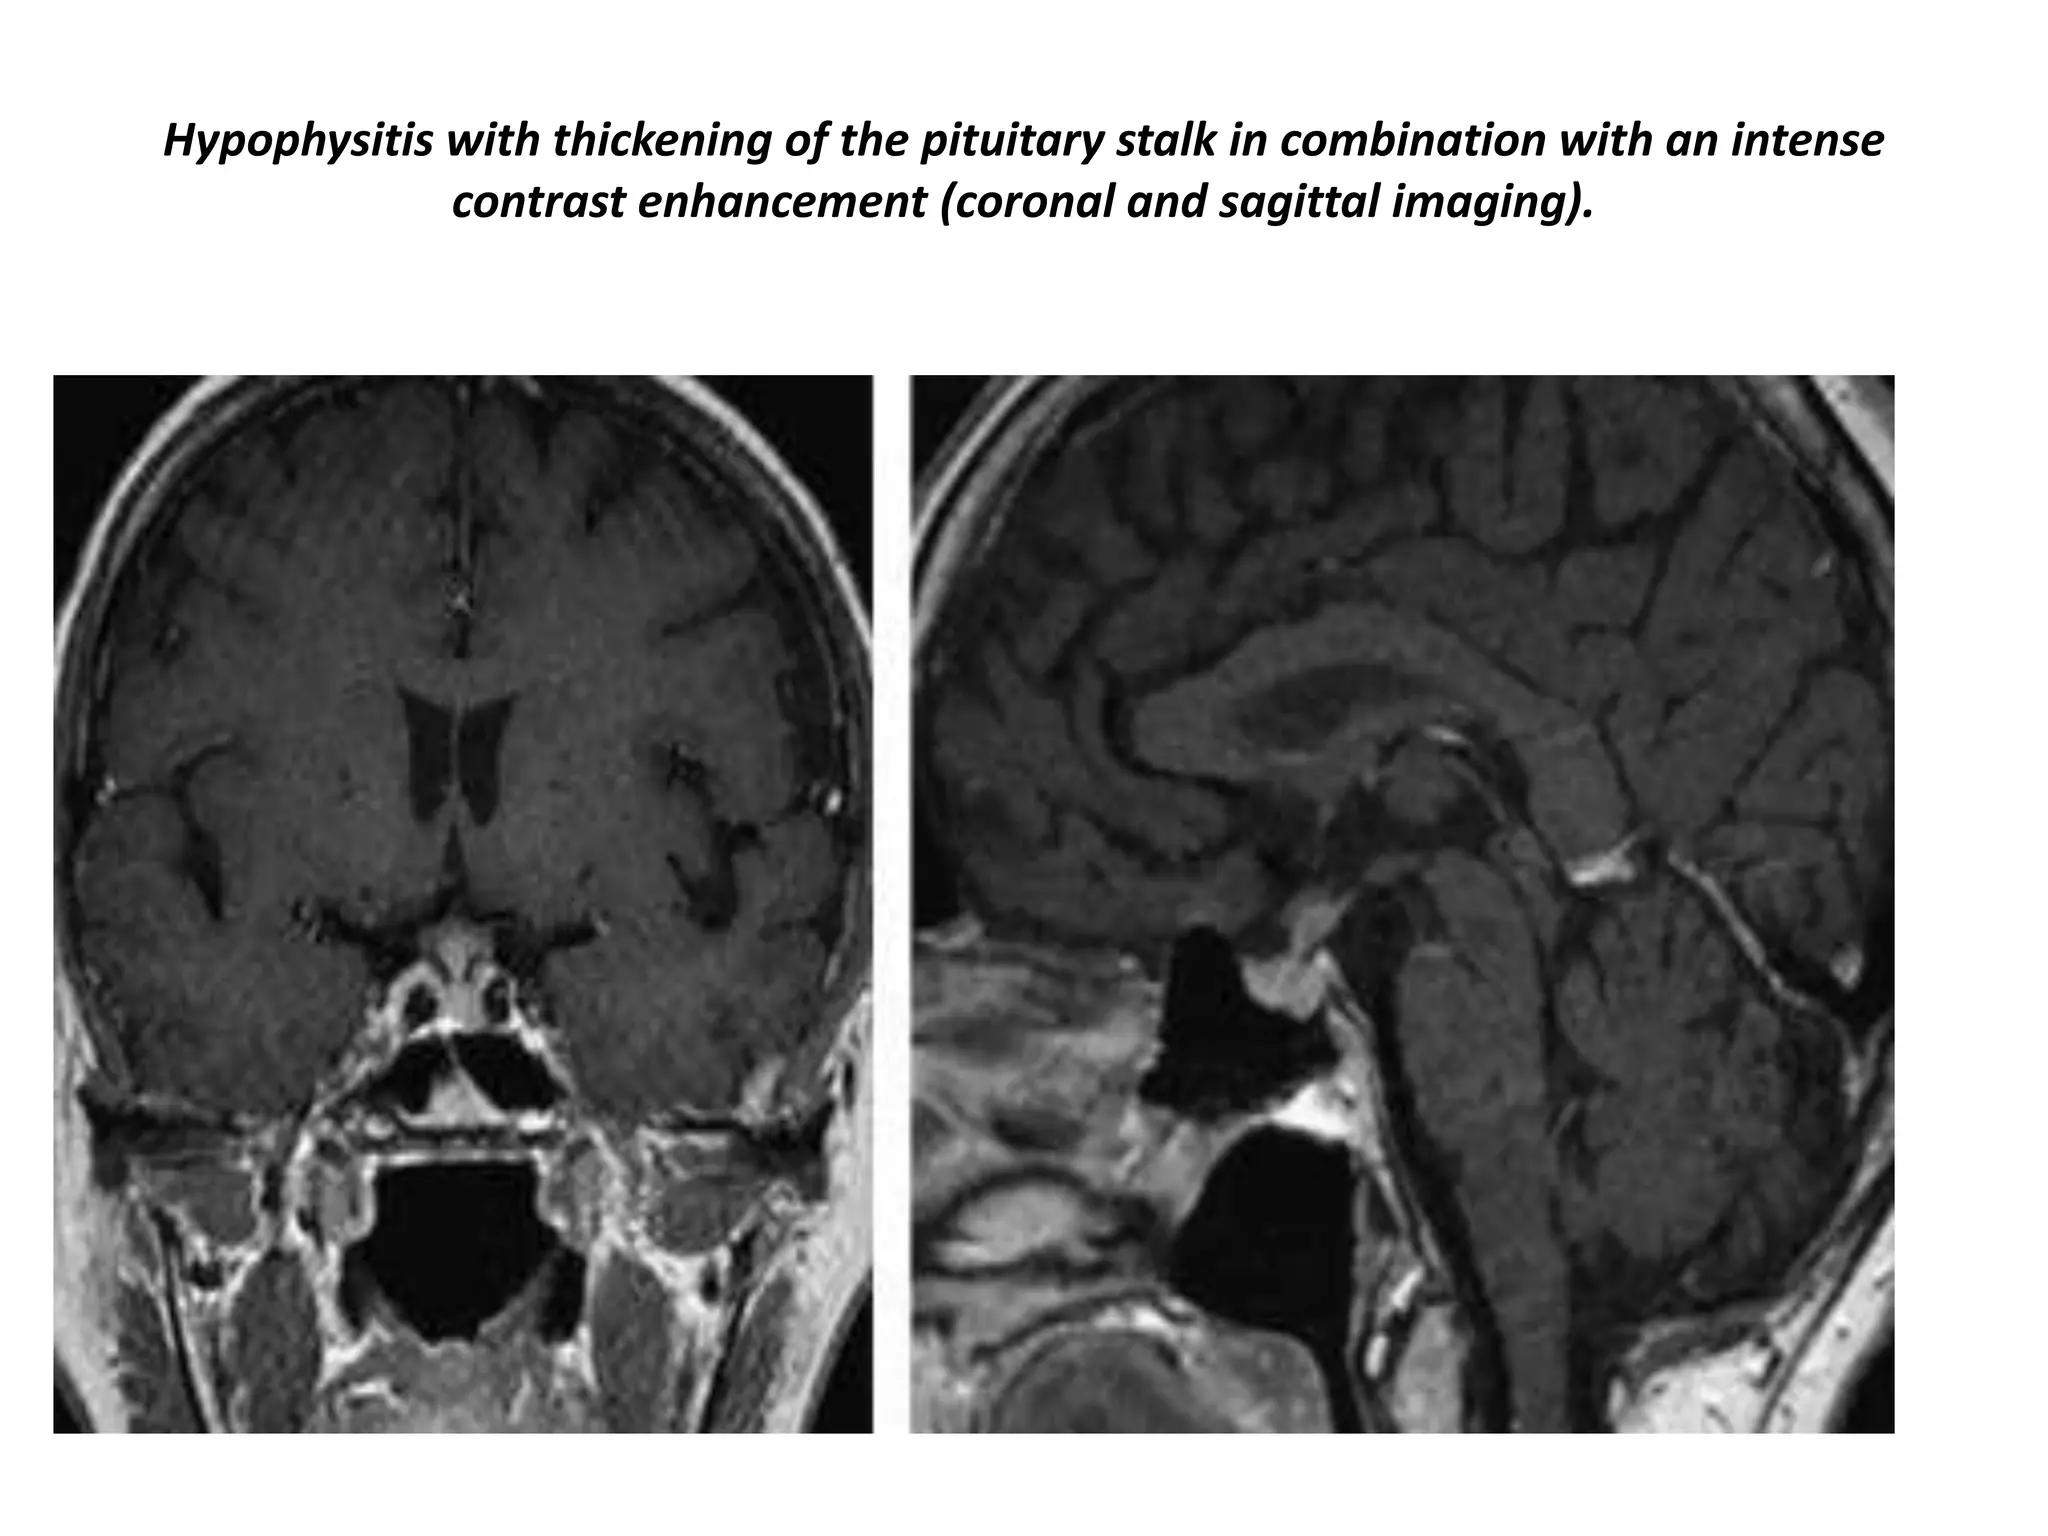

Hypophysitis with thickening of the pituitary stalk in combination with an intense

contrast enhancement (coronal and sagittal imaging).

Hypophysitis sagittal and coronal post-contrast study shows markedly thickened pituitary stalk.